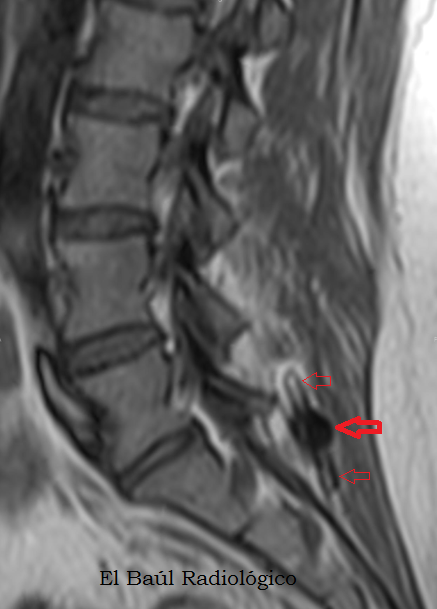

Pr%C3%B3tesis+intersom%C3%A1tica+1.png

FIGURA 6)  En las exploraciones de TRM de columna los implantes se distinguen con mayor dificultad, como una zona oscura intervertebral. Más llamativas  son las bandas brillantes que se producen en el tejido esponjoso de las vértebras adyacentes,  por microfracturas trabeculares (flechas rojas).

(On MRI scans of the spine, the implants are distinguished with difficulty, as an intervertebral dark area. More striking is the finding of bright bands in the cancellous tissue of adjacent vertebrae, produced for trabecular microfractures (red arrows).